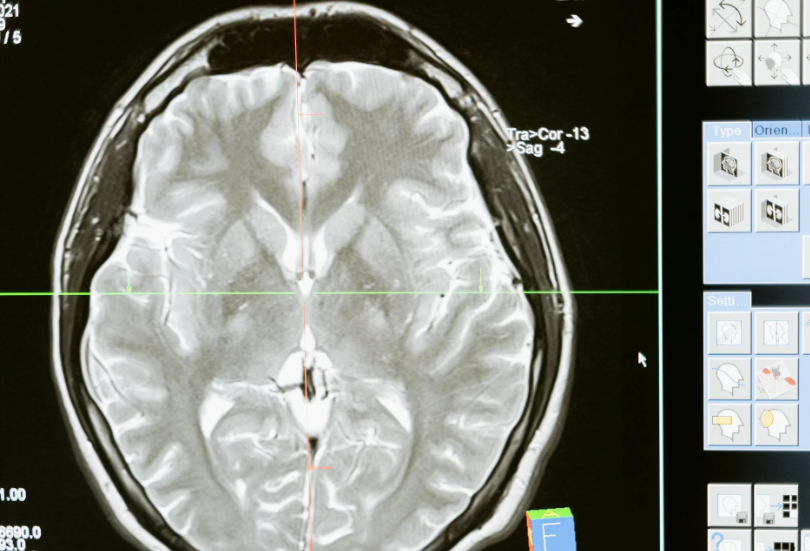

The research compared three groups of participants asked to complete similar writing tasks. One group used ChatGPT, another relied on Google search, and a third worked without any digital assistance. Brain activity was monitored throughout the process.

Participants using AI tools showed significantly lower levels of cognitive engagement, particularly in areas linked to memory, originality, and problem-solving. In contrast, those who worked unaided demonstrated the highest levels of active thinking, while Google users fell somewhere in between.